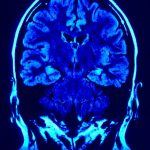

Concussions and other types of traumatic brain injuries have a number of negative physical consequences on youth health. In a new study presented at a national American Academy of Pediatrics conference in Florida, researchers looked at ways to identify how prevalent depression is in children with brain injuries in the United States. Taking data from the 2007 National Survey of Children’s Health, more than 2,000 children with traumatic brain injuries were identified as well as more than 3,100 children with diagnosed depression.

The study found that 15 percent of the children with brain injuries or concussions were also diagnosed with depression. Researchers concluded that depression is two times more likely in children with brain injuries or concussions. This is the largest study to look at the connection between brain injury and depression in children and teens. Researchers hope that the study’s findings may improve how children with brain injuries are identified and treated for depression.

Traumatic brain injury is the leading cause of death and disability in children and teens in the United States, according to the U.S. Centers for Disease Control and Prevention. The two age groups at greatest risk for TBI are age 0 to 4 and 15 to 19. In both those age groups, 62,000 children sustain brain injuries requiring hospitalization as a result of car accidents, falls, sports injuries, physical abuse, etc. Also, 564,000 children each year are seen in hospital emergency departments for brain injuries and released. Among children 0 to 14 years of age, brain injuries results in 2,685 deaths, 37,000 hospitalizations and 435,000 emergency department visits each year.